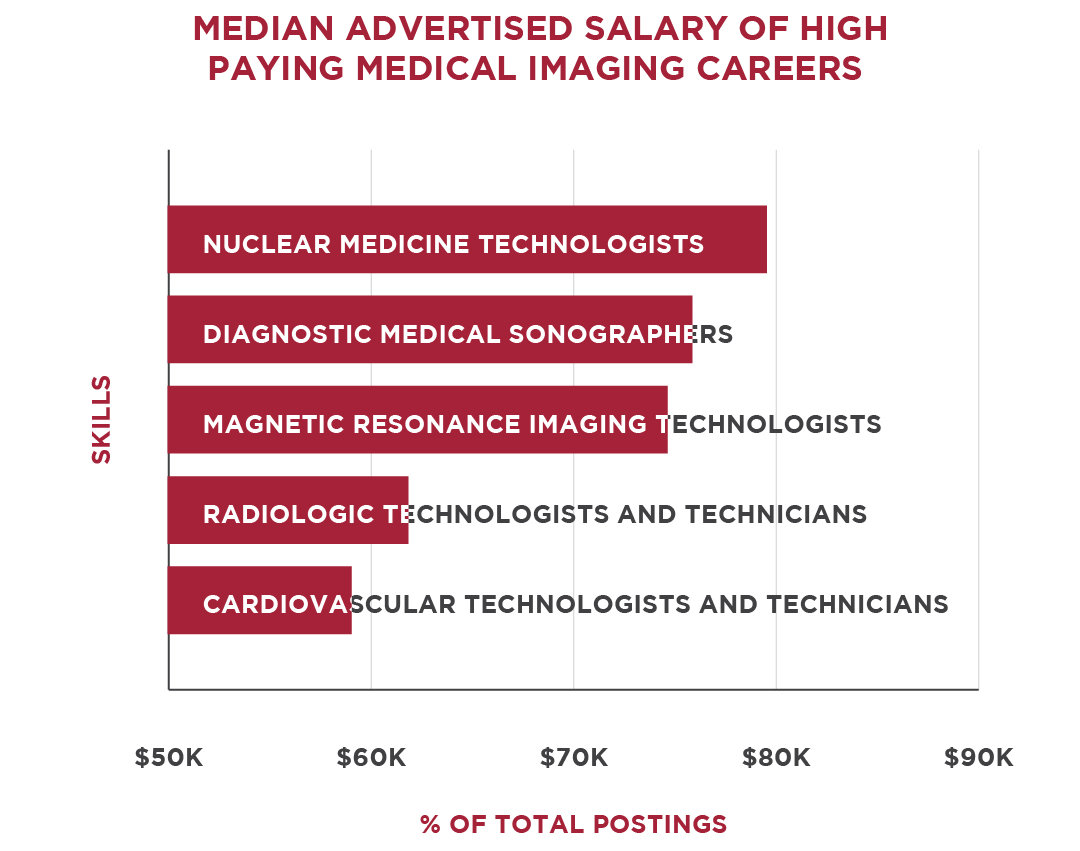

Printable Cute Cats Birthday Card Template For Kids Inkpx free download including neurodiagnostic technologist salaries: what you should know aims the highest paying careers in the medical imaging industry regis college. Careers in neuroscience: what to do with your degree the campus career coach neurodiagnostic technologist salaries: what you should know aims. Jobs salary for a neuroscience major jobs salary for a neuroscience major. The highest paying careers in the medical imaging industry regis college 10 highest paying neuroscience jobs to consider 2022. 10 highest paying neuroscience jobs to consider 2022 10 highest paying neuroscience jobs to consider 2022.

mri tech schools programs salaries jobs salary for a neuroscience major. Neurodiagnostic technologist salaries: what you should know aims mri arrt. Magnetic resonance technologist: occupations in alberta alis day in the life of an mri technologist youtube. L santiago medina pina c sanelli jeffrey g jarvik editors improving the quality of neuroimaging in patient care how can i become an mri tech aims education. Bioinformatics jobs: how to succeed in this competitive space xtalks a high density electroencephalography study reveals abnormal sleep homeostasis in patients with rapid eye movement sleep behavior disorder scientific reports.

pdf improving efficiency in neuroimaging research through application of lean principles noninvasive fluorescence based brain imaging. Comparison shopping: is neuropsychological evaluation more expensive than neuroimaging jobs salary for a neuroscience major. Ariel gilad arielgilad twitter comparing eeg technicians to other neurology careers aims education. List of careers in neuroscience resting state neuroimaging unravels functional organization in the brain. Harmen gudde harmengudde twitter talking brains: 2009.